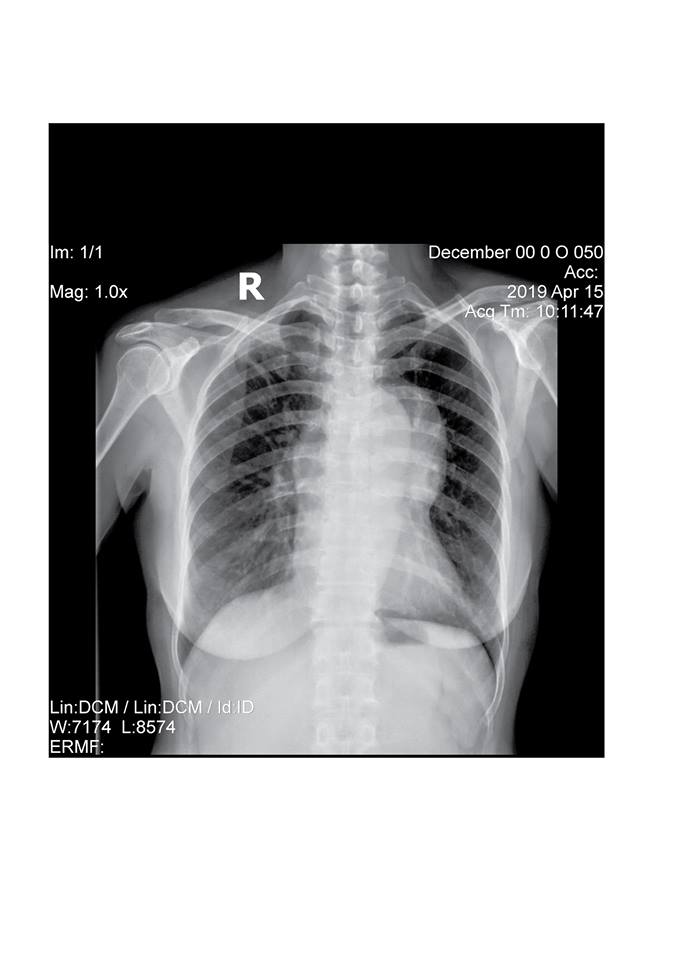

Tại Bệnh viện Medic Bình Dương, bệnh nhân đã được Bác sĩ chuyên khoa thăm khám và chỉ định đi chụp X- Quang ngực thẳng. Sau khi có kết quả, Bác sĩ nghi ngờ có dấu hiệu bất thường ở trung thất, đã hội chẩn và cho chỉ định chụp CT cắt lớp vi tính Lồng ngực kỹ thuật cao với máy CT Scanner 32 lát của hãng GE Mỹ 2017

Sau khi chụp CT, phát hiện có một khối choán chỗ trung thất trước to, làm cho bệnh nhân ho kéo dài, khó thở, tức ngực. Chẩn đoán đây là trường hợp U quái trung thất nên đã chuyển lên tuyến trên để phẫu thuật kịp thời.